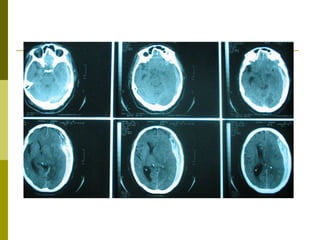

Clasificación Tomográfica del TEC según el National Traumatic Coma Data Bank (TCDB)  Grado, Tipo de lesión, TAC craneal I  Lesión difusa I  Sin patología visible en la TAC II  Lesión difusa II  Cisternas presentes con desplazamientos de la línea media de 0-5 mm y/o lesiones densas presentes. Sin lesiones de densidad alta o mixta > 25 cm3. Puede incluir fragmentos óseos y cuerpos extraños. III  Lesión difusa III (Swelling)  Cisternas comprimidas o ausentes con desplazamiento de la línea media de 0-5 mm. Sin lesiones de densidad alta o mixta > 25 cm3. IV  Lesión difusa IV (Shift)  Desplazamiento de la línea media > 5 mm. Sin lesiones de densidad alta o mixta > 25 cm3. V  Lesión focal evacuada  Cualquier lesión evacuada quirúrgicamente. VI  Lesión focal no evacuada  Lesión de densidad alta o mixta >25 cm3 no evacuada quirúrgicamente. Marshall L., Gautille R, Klauber M et al. The outcome of severe closed head injury. J. Neurosurg. 75 (S):528.1991.

Resultados Según la clasificación tomográfica del TEC, las lesiones  más frecuentes fueron:  Categoría VI TCDB: 10 - 28%.  Categoría V TCDB:  7 – 19% Categoría IV TCDB: 1 –3% Hematoma Extraaxial: 12 – 33%  Lesiones mixtas:  14 – 39%

Resultados Pacientes con TEC: Contusión Hemorrágica: 10 Contusión Hemorrágica + HSD: 9 HSD: 7 HED: 5 Contusión Hemorrágica + HED: 3 Contusión Hemorrágica + HSD + HED: 1 HED + HSA: 1

Resultados Pacientes con ACV Hematoma Intraparenquimal: 7 Infarto: 1

Clasificación Tomográfica delTEC según el National Traumatic Coma Data Bank (TCDB) Grado, Tipo de lesión, TAC craneal I Lesión difusa I Sin patología visible en la TAC II Lesión difusa II Cisternas presentes con desplazamientos de la línea media de 0-5 mm y/o lesiones densas presentes. Sin lesiones de densidad alta o mixta > 25 cm3. Puede incluir fragmentos óseos y cuerpos extraños. III Lesión difusa III (Swelling) Cisternas comprimidas o ausentes con desplazamiento de la línea media de 0-5 mm. Sin lesiones de densidad alta o mixta > 25 cm3. IV Lesión difusa IV (Shift) Desplazamiento de la línea media > 5 mm. Sin lesiones de densidad alta o mixta > 25 cm3. V Lesión focal evacuada Cualquier lesión evacuada quirúrgicamente. VI Lesión focal no evacuada Lesión de densidad alta o mixta >25 cm3 no evacuada quirúrgicamente. Marshall L., Gautille R, Klauber M et al. The outcome of severe closed head injury. J. Neurosurg. 75 (S):528.1991.

Resultados Según laclasificación tomográfica del TEC, las lesiones más frecuentes fueron: Categoría VI TCDB: 10 - 28%. Categoría V TCDB: 7 – 19% Categoría IV TCDB: 1 –3% Hematoma Extraaxial: 12 – 33% Lesiones mixtas: 14 – 39%

Resultados Pacientes conTEC: Contusión Hemorrágica: 10 Contusión Hemorrágica + HSD: 9 HSD: 7 HED: 5 Contusión Hemorrágica + HED: 3 Contusión Hemorrágica + HSD + HED: 1 HED + HSA: 1

Resultados Pacientes conACV Hematoma Intraparenquimal: 7 Infarto: 1